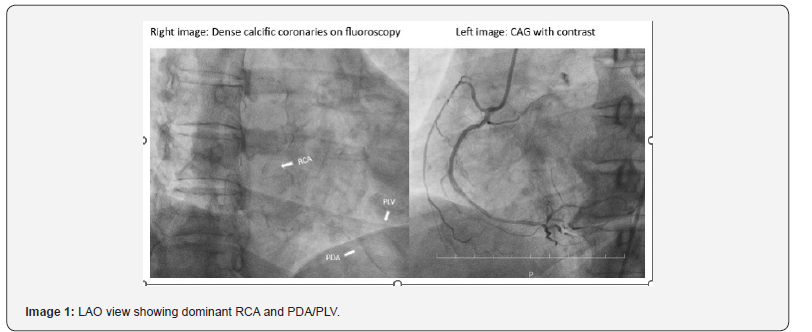

Coronary Angiogram: Suggestive of LMCA + Triple vessel disease (Images 1,2,3)

RCA – (Dominant) Thick calcific vessel, proximal mild disease, mid long segment 60% stenosis, distal 60-70% stenosis PDA/PLV diseased